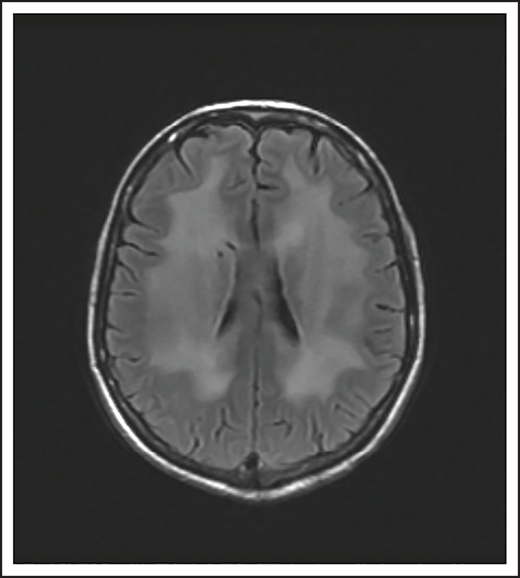

A 25-year-old man presented with fatigue with abdominal and bone pain, evaluation of which led to the diagnosis of a high-grade DLBCL with MYC and BCL2 rearrangements. Upon completion of treatment with 6 cycles of R-EPOCH (rituximab-etoposide, prednisone, vincristine, cyclophosphamide, and doxorubicin) and prophylactic intrathecal (IT) methotrexate, he developed severe pain in his right shoulder and left leg, associated with numbness of his left foot. Over the next month, his symptoms progressed, and he developed worsening pain and weakness in the right arm and bilateral foot drop. He was then diagnosed with Parsonage-Turner syndrome, an idiopathic brachial plexopathy, and treated with methylprednisolone, which did not help. Subsequently, an MRI of the brachial plexus showed increased enhancement and FDG-PET scan showed increased uptake in the right brachial plexus and bilateral sciatic nerves (Figure 1). Finally, he was diagnosed with neurolymphomatosis. He responded to treatment with HD-MTX and cytarabine and made a full recovery.

Brachial plexus MRI and FDG-PET scan of a patient with neurolymphomatosis. (A) An axial T1-weighted image after gadolinium contrast shows enhancement of the right brachial plexus. (B) FDG-PET scan shows an increase in FDG uptake in the right brachial plexus.